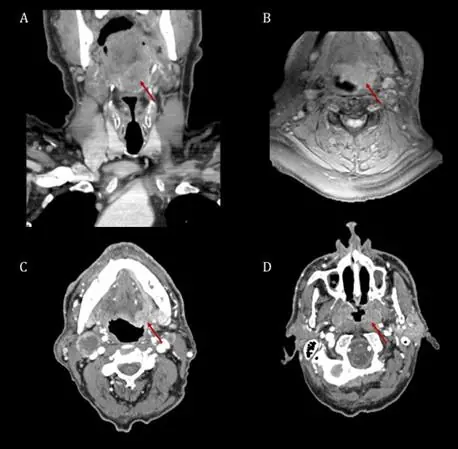

Casos clínicos de tumores de Orofaringe.

En el ámbito clínico, la detección temprana y precisa de carcinomas epidermoides de orofaringe es crucial para mejorar los resultados del paciente. Os presentamos dos casos clínicos de carcinomas epidermoides de orofaringe, abordados mediante la aplicación de nuestra checklist previamente validada, diseñada para facilitar el diagnóstico y la evaluación de esta patología.